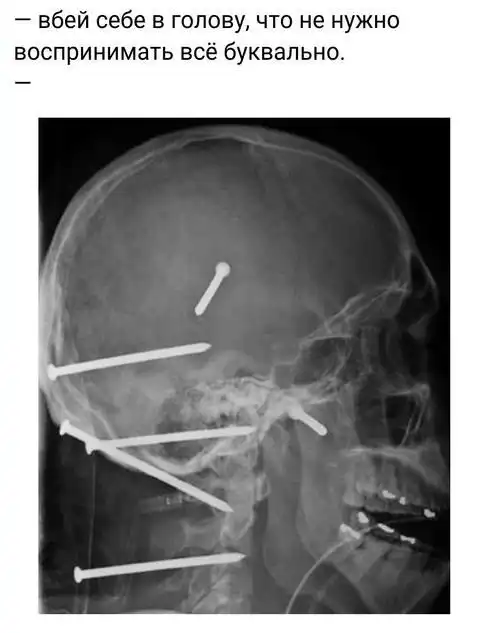

Вбей себе в голову